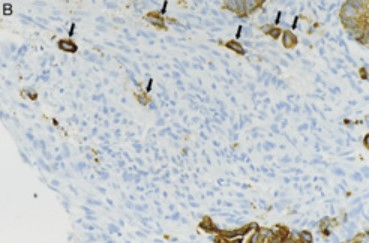

By Farzad Hoque, Class of 2028 On the battlefield, the adjacent role of nanocarriers is logistical. They provide munitions support and focused attention to the battlefield. In the body, the focus is on how these nanocarriers can improve the fight against cancer–specificity, reduce toxicity, and sustain the efficacy of immunological agents–all by modulating the antitumor immune response. In prior wars with cancer, the body’s arsenal … Continue reading Battlefront: The Nano DLC